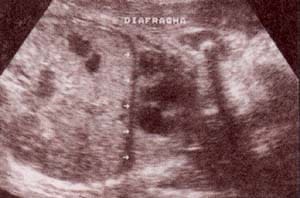

fig 27.– (a). diafragma. |

fig. 27. – (b). (a y b). cortes longitudinales (a las 33 y 38 semanas), de la cúpula diafragmática, poco ecogénica que delimita el área pulmonar y hepática |